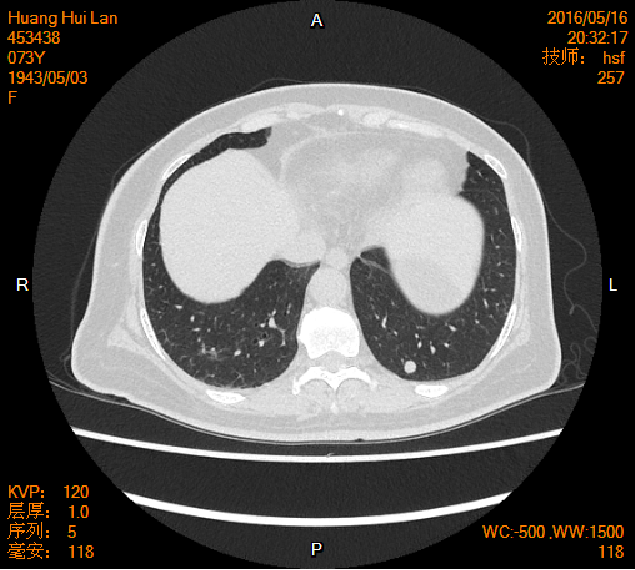

2016-04-13胸腹盆CT

2016-05-17胸腹盆CT(术后基线)